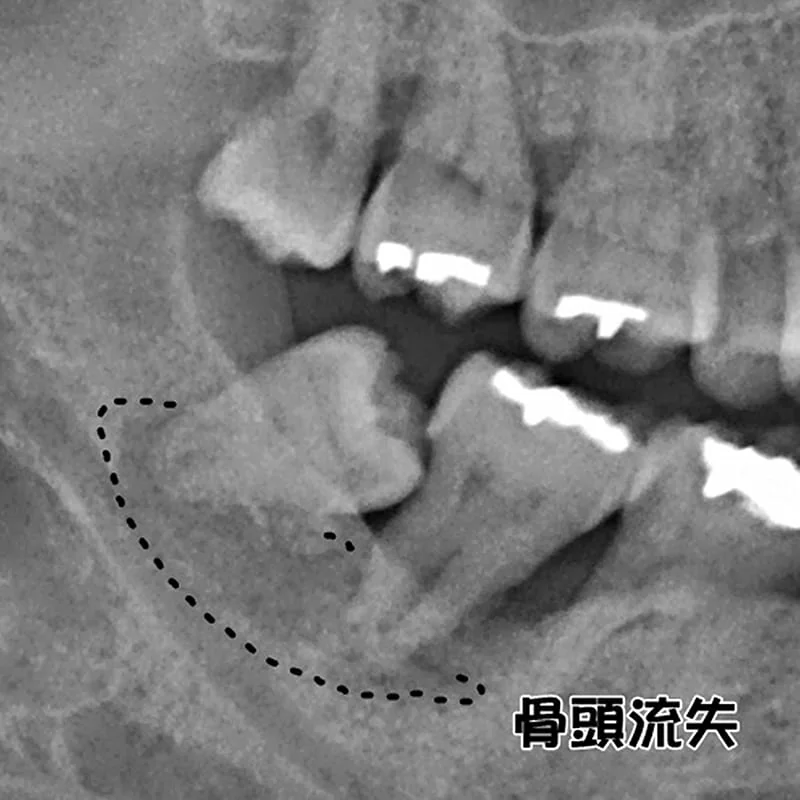

經由X光片顯示,患者右下的第二大臼齒及第三大臼齒有一區黑影,董建華醫師透過3D電腦斷層,確定患者該區因牙周發炎導致骨頭嚴重流失,牙齒無法正常的咬合,判斷需拔牙,並因為骨頭破壞程度較大的關係,希望日後有足夠垂直向、橫向骨頭,來做人工牙根,所以建議患者可以補骨膠原蛋白,促進傷口癒合及骨質增生。

( 治療前 )

( 治療前:X光片上呈顯黑色暗影 )